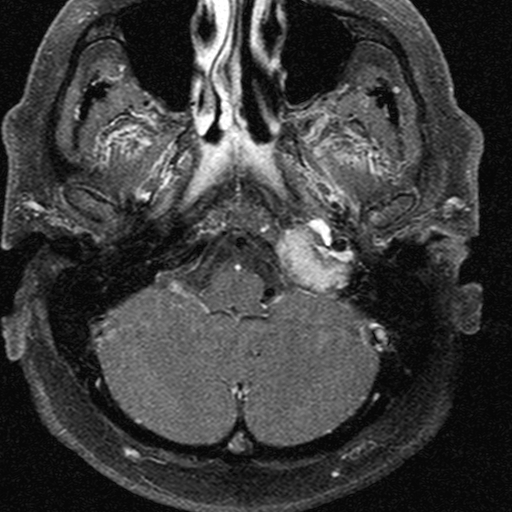

To evaluate soft tissue pathology, mucosal thickening and fluid accumulation, MRI is recommended, especially in the middle and inner ear. MRI plays an important role in inflammatory and tumorous processes, and in their intracranial and extracranial complications. MRI is the modality of choice to assess extracranial and intracranial complications of inflammatory ear disease, including most commonly epidural and cerebral abscesses and sinus thrombosis secondary to chronic otitis media. Examination of the pontocerebellar angle in sensorineural hearing loss is performed by a special thin-slice T2W MRI sequence and postcontrast T1W MRI, since these sequences are capable to detect acoustic neurinoma, while HRCT cannot visualize this abnormality. In some complex diagnostic cases both CT and MRI are needed for accurate diagnosis.

1. image: Patient with sensorineural hearing loss and tinnitus. MR-study (T2, precontrast T1 and postcontrast T1) reveal a mass in the left pontocerebellar angle without significant contrast enhancement. HRCT proves that the mass arises from the petrous pyramid, suggesting cholesterol granuloma. (Asklepios Klinik Altona, Hamburg)